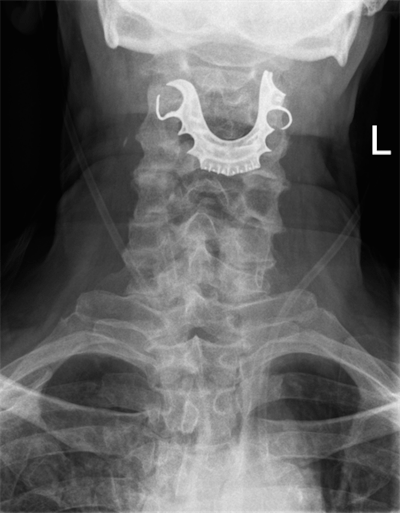

An ENT exam revealed a "metallic semicircular object overlying the vocal cords and completely obstructing their view." When the doctor told this to the patient, he revealed that he had lost his partial dentures during his surgery stay eight days earlier.